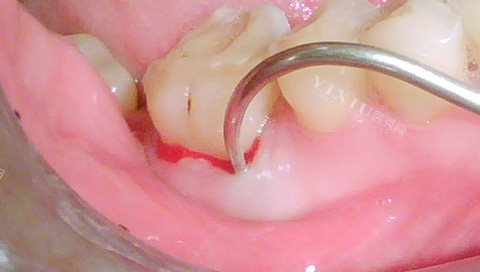

牙龈肿胀:根尖周炎会导致牙根尖周围的牙龈出现肿胀,肿胀一般局限在患牙的根尖部位,严峻时可能扩散到周围牙龈组织。

观察牙齿:观察是否有龋坏、龋洞,牙龈上是否反复出现脓包或瘘管。